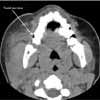

Facial CT scan as shown.

Facial CT revealed a 3-mm calcification in the distal portion of the parotid duct, diffuse enlargement of the parotid gland, and regional lymph node enlargement. After a dose of ampicillin/sulbactam, the patient was discharged with pain medication and a prescription for oral antibiotics. She was advised to apply warm compresses and to suck on sialogogues (sour candy). Follow-up with an otolaryngologist in 7 days was also recommended.